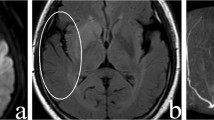

Illustrative case of arterial hyperintensity with multimodality images

A 62-year-old man presented with left-sided weakness with an initial NIHSS score of 10. CT angiography and digital subtraction angiography showed occlusion in the right MCA, insular segment. Hyperintense artery was visualised distal to the occlusion site on post-contrast 3D T1W BB FSE, and not on the pre-contrast study. The velocity of hyperintense artery appeared to be slower than that of the vein, since the signal intensity of the posterior superior sagittal sinus was suppressed. Hyperintense artery was well matched with the retrograde collateral flow on digital subtraction angiography (Fig. 1).

a Maximum intensity projection image of CT angiography shows occlusion in the right MCA, insular segment (arrow). b Maximum intensity projection image of Gd-enhanced 3D T1W BB FSE shows hyperintense arteries (arrowheads) distal to the occlusion site. c Angiography in early phase shows occlusion in the right MCA, insular segment. d Retrograde collateral flow is filled in the delayed phase at the region where the hyperintense artery is seen. Hyperintense artery is not seen on the pre-contrast (e) but on the post-contrast 3D T1W BB FSE (f)